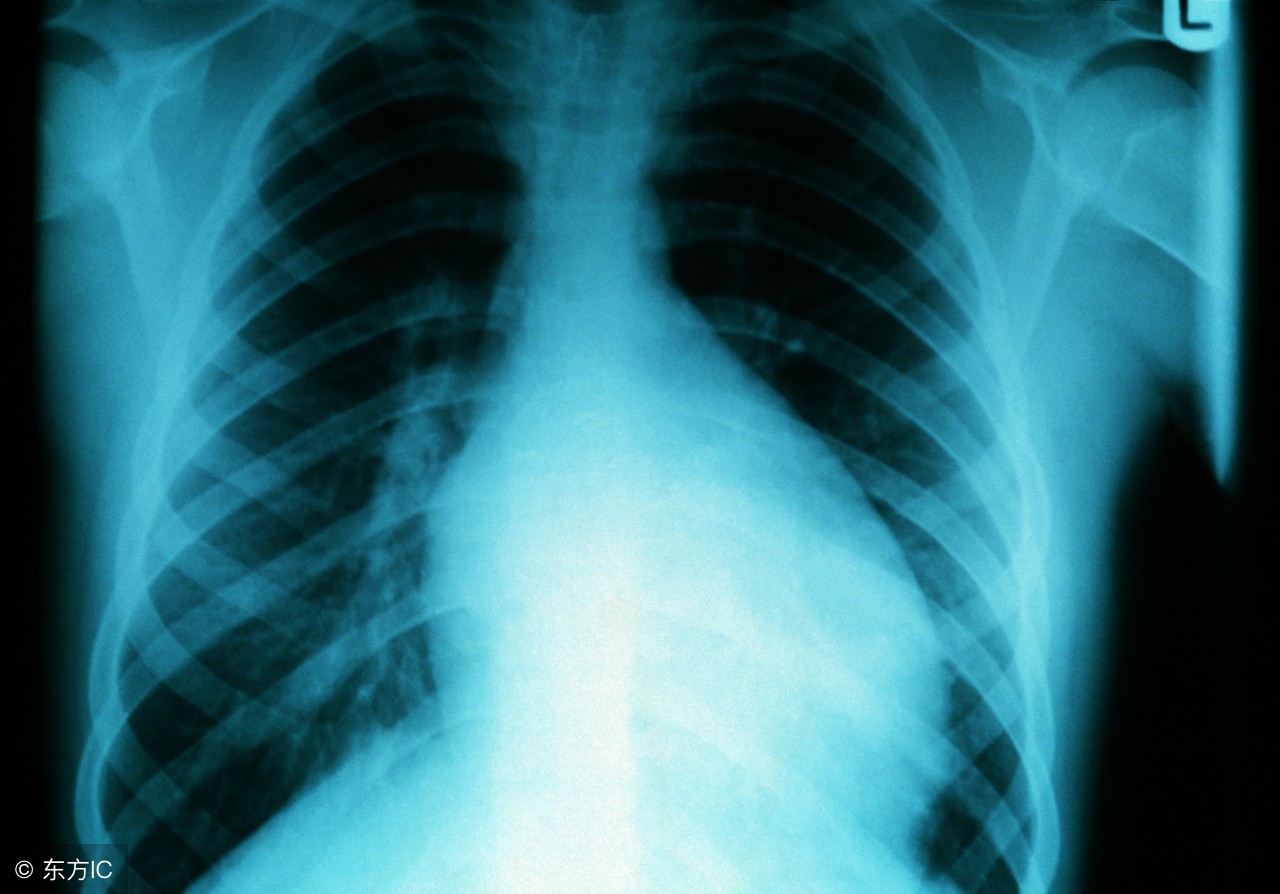

心肌炎主要是指心肌本身的炎性病变,有时会有弥漫性以及局灶性、急性慢性之分。近些年来病毒性心肌炎成为主要的发病种类,主要是因为人们长期的生活不规律、工作学习压力大造成的,心肌炎在临床上分为感染性以及非感染性两种。